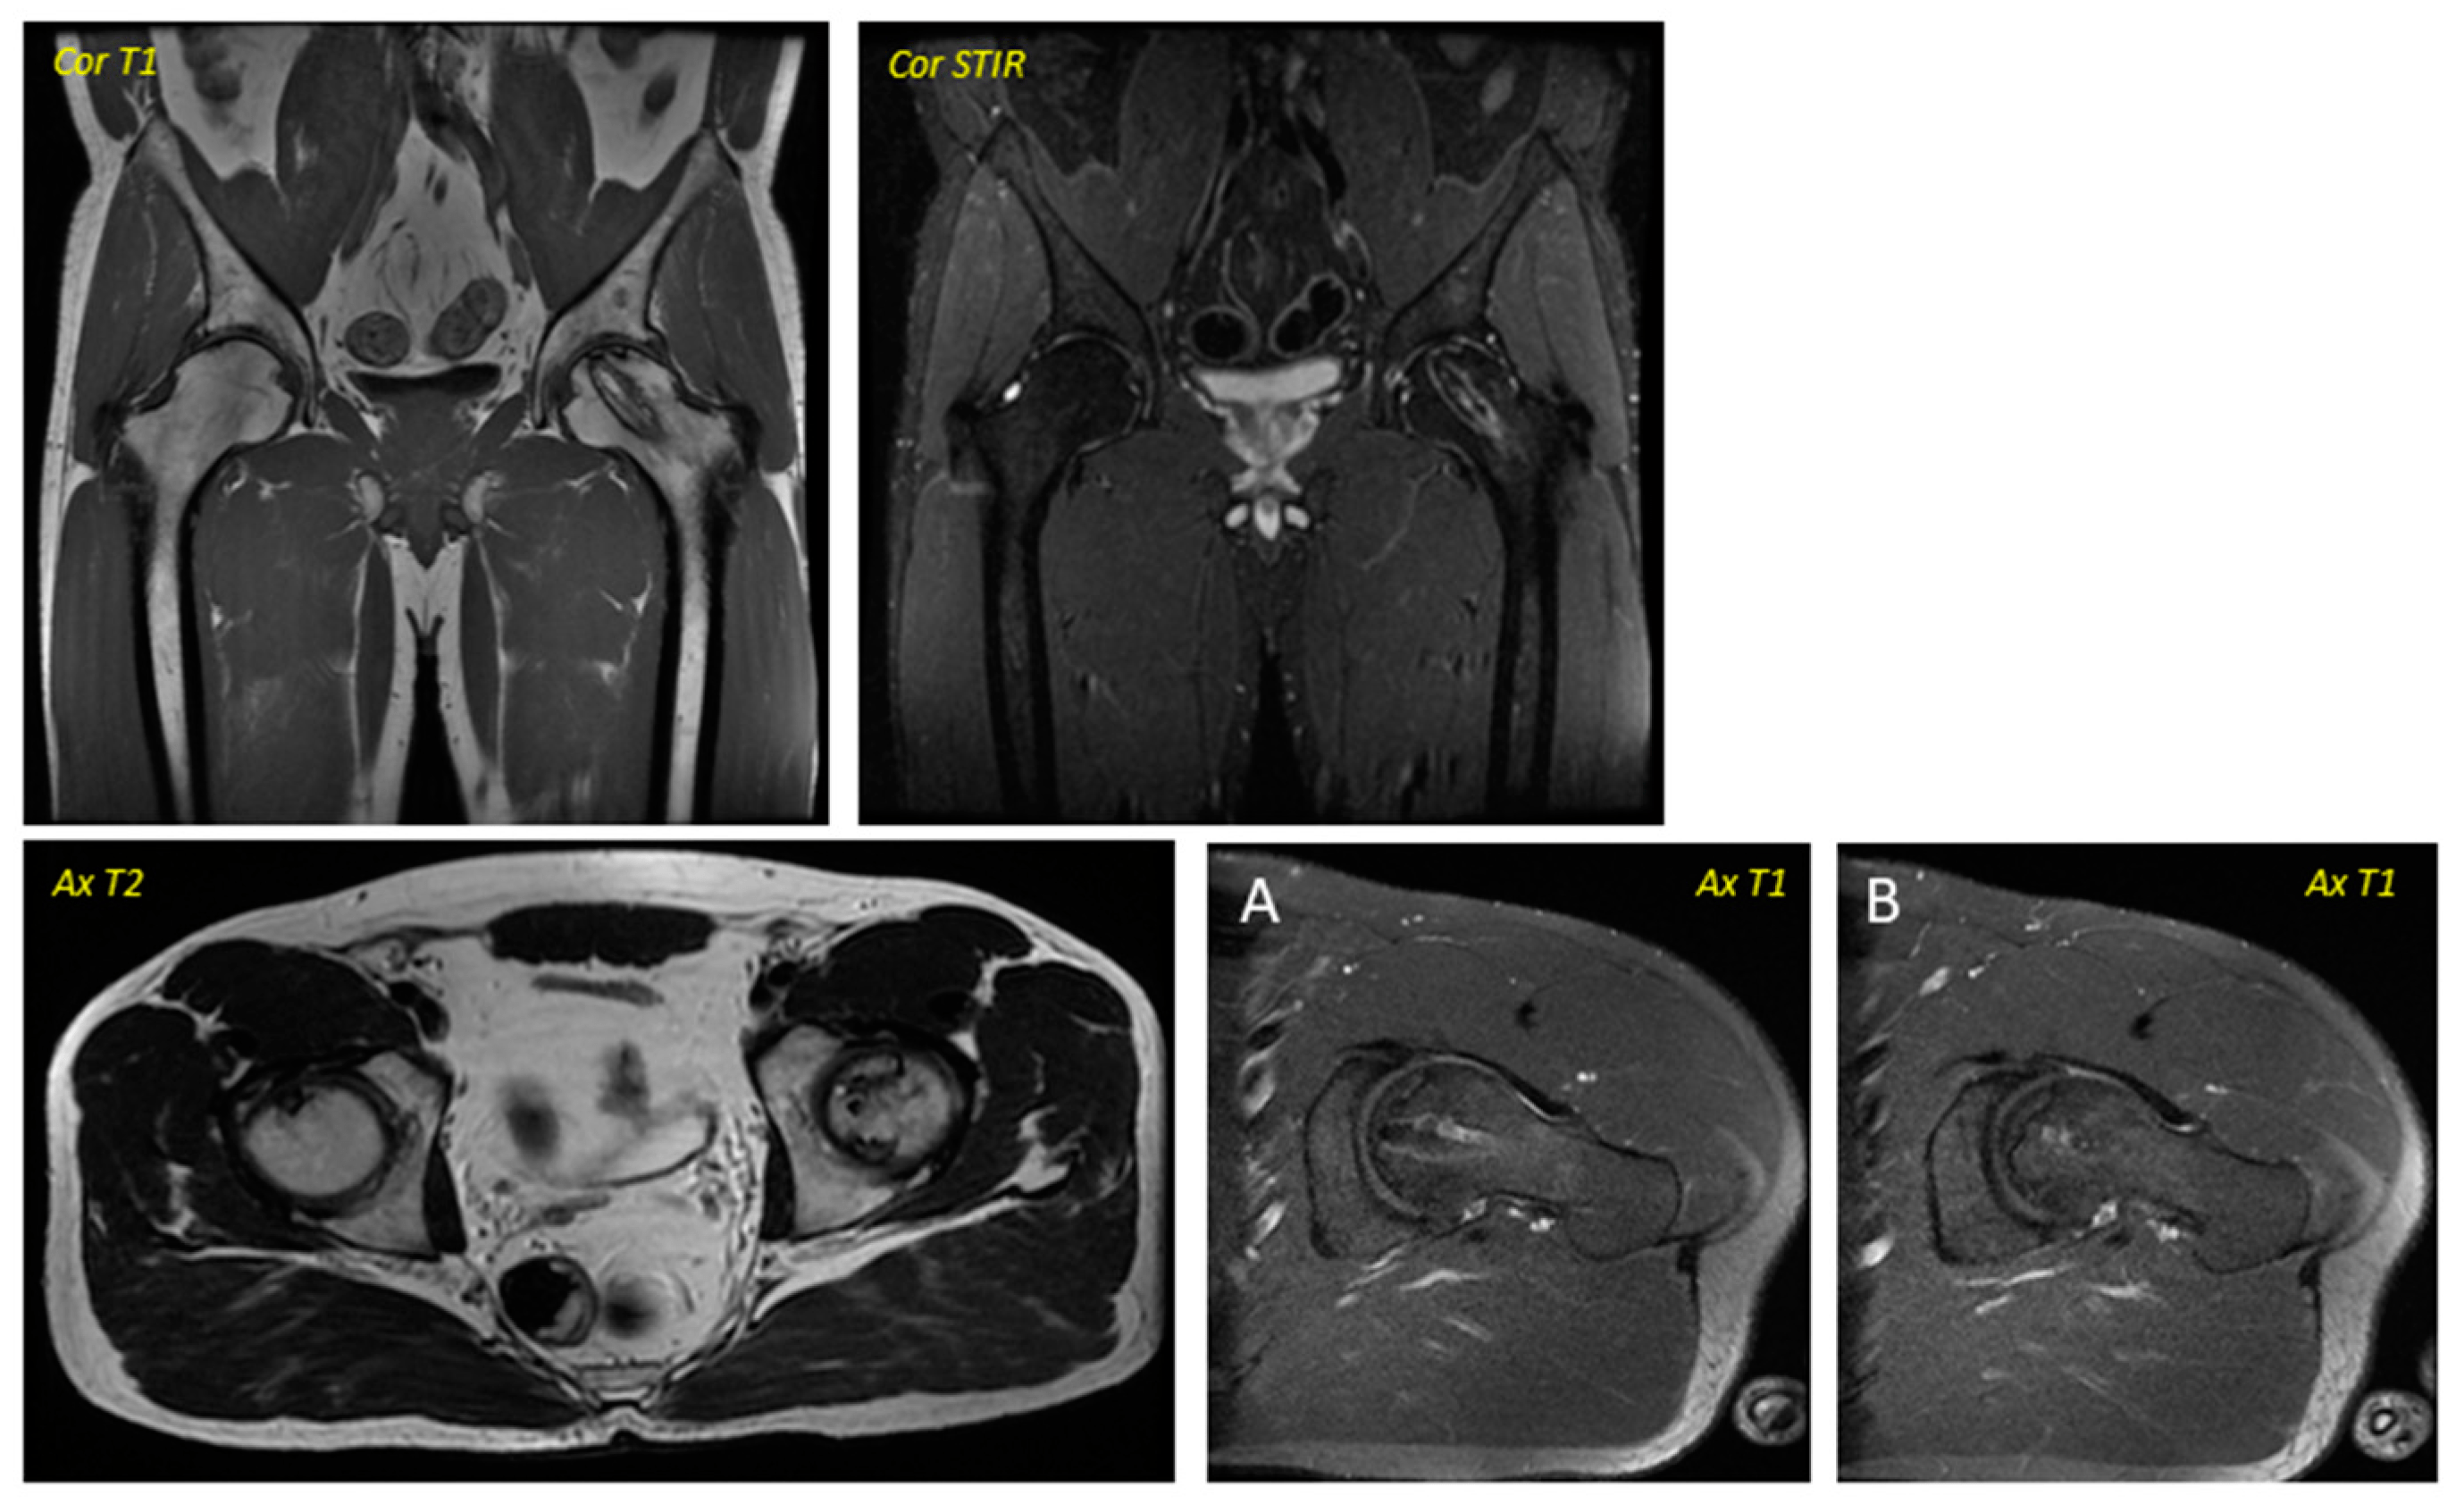

關于影像學研究,在12個月的隨訪期間,在影像學演變中觀察到了一些發現(圖1和圖2)。

首先,方向的變化從第六個月開始出現在所有病例中,而在早期階段并不明顯。其次,62.5%的患者 ( n=5) 在手術后的第一年內實現了影像穩定。第三,兩名患者 (25%) 出現壞死區進展,而一名 (12.5%) 患者出現明顯的再骨化跡象。盡管觀察到描述性差異,但后一個參數的p值在統計學上并不顯著。